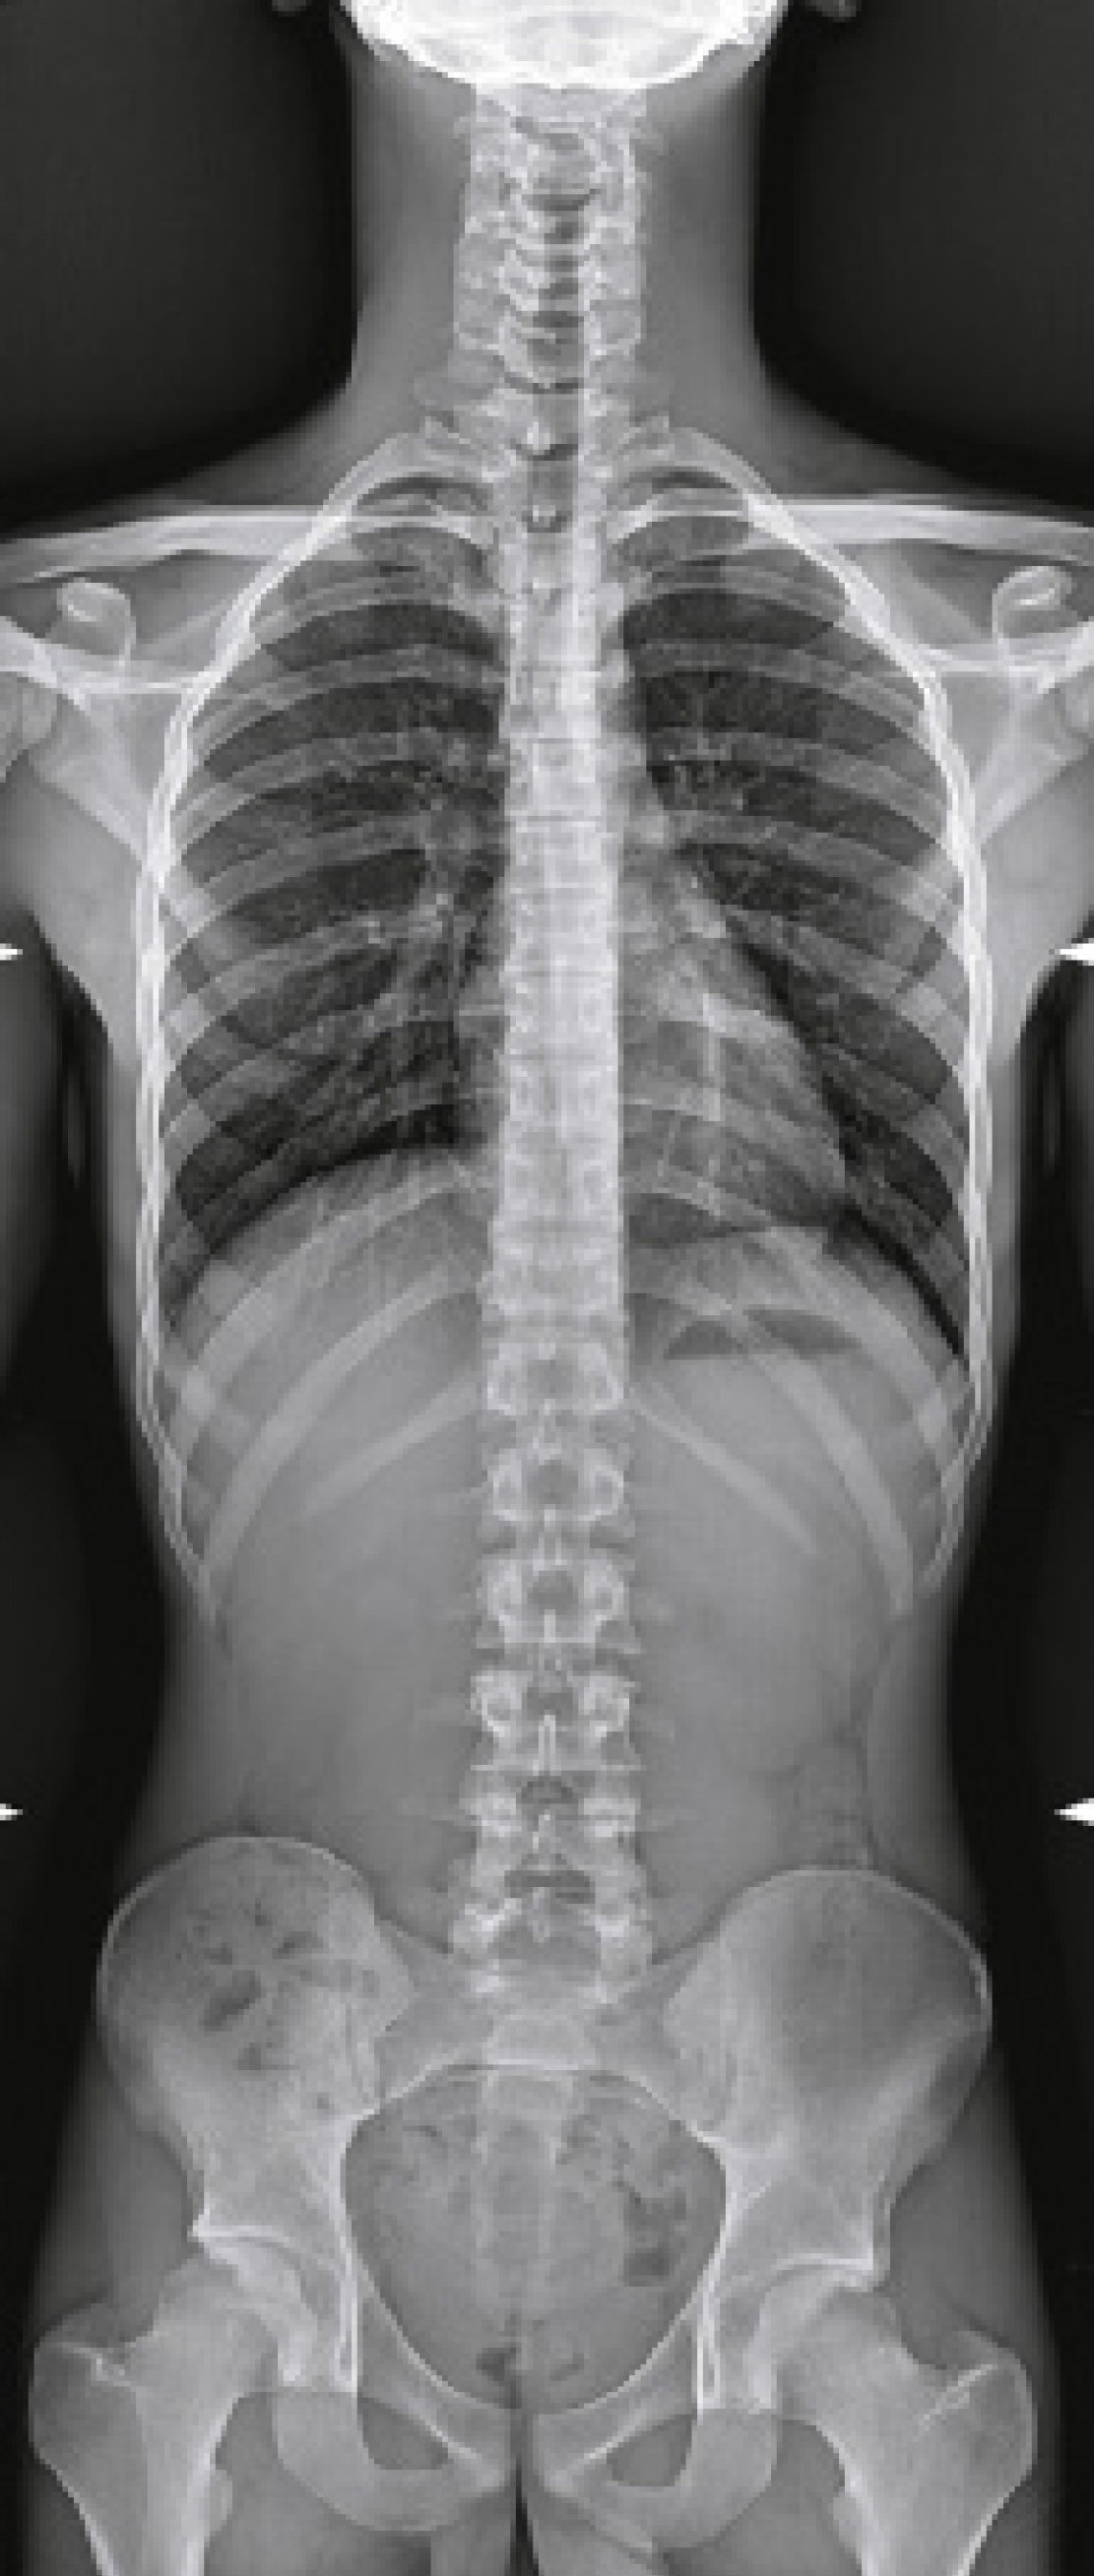

Аппарат позволяет проводить исследования как детей, так и взрослых, обладает максимальными возможностями в части охвата в продольном и поперечном направлениях, проведении исследований без перемещения пациента, выбора фокусного расстояния, наклона и поворота излучателя. Продуманная конструкция комплекса дает возможность свободно подходить к столу с любой стороны, а габариты и большой диапазон изменения высоты деки облегчает процесс укладки пациентов, что очень удобно для позиционирования пожилых и травмированных пациентов, людей с ограниченными возможностями, детей.

- Различные режимы съемки: рентгенография, рентгеноскопия, линейная томография, томосинтез, сшивка